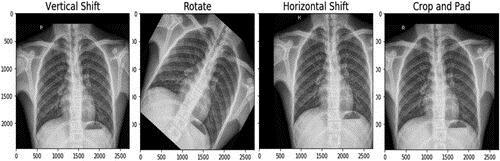

The initial dataset from the Guangzhou Women and Children'sMedicalCenterhad5836imagesaltogether.Both healthyindividualsandpneumoniapatientsweredepicted in the pictures. There were 1583 photographs of healthy chest X-rays and 4273 images of chest X-rays with pneumonia.Atrainingsetwith5136imagesandatestset with700imageswerecreatedfromtheentiredataset.The figureshowsthefirsttwoexampleimagesfromthedataset.

This research suggests an ideal strategy for detecting pneumoniafromchestX-rays.Toexpandthesmalldataset, dataaugmentationtechniqueswereused.

5.1 PRE-PROCESSING AND DATA AUGMENTATION

Theinputphotoswerefirstreducedinsizeto224*224and used to train the model. A sizable dataset is necessary for efficientneuralnetworktraining.Becausethedeepnetworks cannotgeneralizewhentrainedonasmallerdataset,testing accuracysuffers.Oneapproachtosolvingthisissueisdata augmentation,whichextendsandeffectivelymakesuseof the current dataset. There were 1283 healthy chest X-ray images and 3873 pneumonia-infected chest X-ray case imagesinthetrainingdatasetusedinthisstudy.Sincethe datasetalreadycontainedadequatephotosofthepneumonia

case, just the images of the normal case needed to be enhancedtwice.Therewere3849normalpicturesand3873 photosofpneumoniafollowingaugmentation.Imagesfrom thetestsetwerenotenhanced.

Figure1:ChestX-rayofahealthyperson(a)andaperson sufferingfrompneumonia(b). Figure2:Resultantimagesafterusingaugmentation techniques.